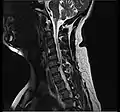

The majority of spinal disc herniations occur in the lumbar spine (95% at L4–L5 or L5–S1).[21] The second most common site is the cervical region (C5–C6, C6–C7). The thoracic region accounts for only 1–2% of cases. Herniations usually occur postero-laterally, at the points where the annulus fibrosus is relatively thin and is not reinforced by the posterior or anterior longitudinal ligament.[21] In the cervical spine, a symptomatic postero-lateral herniation between two vertebrae will impinge on the nerve which exits the spinal canal between those two vertebrae on that side.[21] So, for example, a right postero-lateral herniation of the disc between vertebrae C5 and C6 will impinge on the right C6 spinal nerve. The rest of the spinal cord, however, is oriented differently, so a symptomatic postero-lateral herniation between two vertebrae will impinge on the nerve exiting at the next intervertebral level down.[21]

Cervical disc herniation

Herniated disc at C6–C7 level

Cervical disc herniations occur in the neck, most often between the fifth and sixth (C5–6) and the sixth and seventh (C6–7) cervical vertebral bodies. There is an increased susceptibility amongst older (60+) patients to herniations higher in the neck, especially at C3–4.[23] Symptoms of cervical herniations may be felt in the back of the skull, the neck, shoulder girdle, scapula, arm, and hand.[24] The nerves of the cervical plexus and brachial plexus can be affected.[25]

• Magnetic resonance imaging is the gold standard study for confirming a suspected LDH. With a diagnostic accuracy of 97%, it is the most sensitive study to visualize a herniated disc due to its significant ability in soft tissue visualization. MRI also has higher inter-observer reliability than other imaging modalities. It suggests disc herniation when it shows an increased T2-weighted signal at the posterior 10% of the disc. Degenerative disc diseases have shown a correlation with Modic type 1 changes. When evaluating for postoperative lumbar radiculopathies, the recommendation is that the MRI is performed with contrast unless otherwise contraindicated. MRI is more effective than CT in distinguishing inflammatory, malignant, or inflammatory etiologies of LDH. It is indicated relatively early in the course of evaluation (<8 weeks) when the patient presents with relative indications like significant pain, neurological motor deficits, and cauda equina syndrome. Diffusion tensor imaging is a type of MRI sequence used for detecting microstructural changes in the nerve root. It may be beneficial in understanding the changes that occur after herniated lumbar disc compresses a nerve root, and might help in differentiating the patients that need surgical intervention. In patients with a high suspicion of radiculopathy due to lumbar disc herniation, yet the MRI is equivocal or negative, nerve conduction studies are indicated.[44] T2-weighted images allow for clear visualization of protruded disc material in the spinal canal.